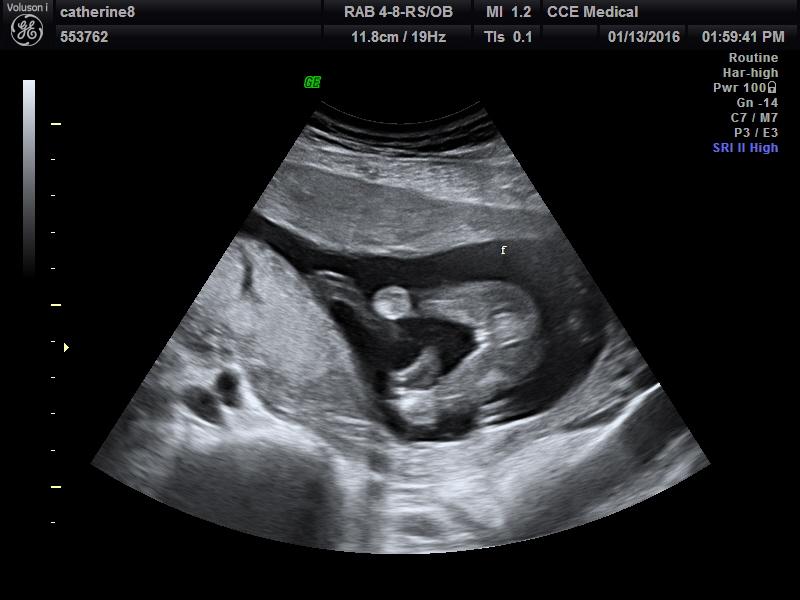

Attachment 29319Attachment 29320Attachment 29321Attachment 29322

Snuck to a private scan at 16 weeks 3 days. No chance in gender changing right??

Huge congrats Mommymachine! I knew you had a pinkie growing in there! Yay [emoji175]!!

All girl! Imagine, 3 girls after 3 boys!

Congrats :). That's a girl all the way! 3 successful sways! That's amazing! Xx.

Congratulations mommy that there is FOR SURE your 3rd little girly :) enjoy her & congrats:) you got this swaying nailed!!!!